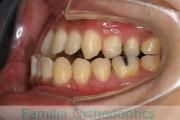

No.22V-409

- 叢生

- 16歳

- 女性

- 抜歯部位

- 上:

- 44

- 下:

- 8|58

- 主な使用装置:

- FEA

- 治療にかかった費用:

- 86万円

八重歯を治したいということで来院されました。下あごの左ずれのある上顎前突(出っ歯)・叢生(でこぼこ)でしたので、上は左右から、下はで左のみ小臼歯を抜歯して、歯科矯正用アンカースクリューとマルチブラケット法にて治療を行いました。2年強、30回程度の通院が必要でした。

上下とも前歯の叢生(でこぼこ、凹凸、ガタガタ)があるため、保定を怠ると後戻りのリスクがあります。